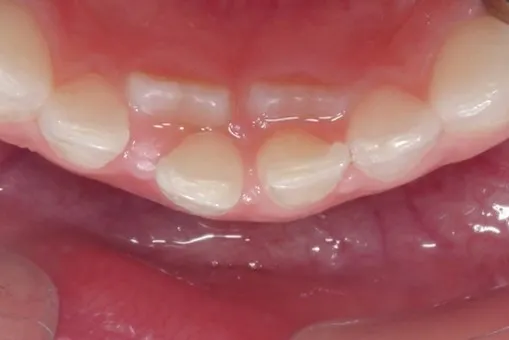

下排有兩排牙齒 -- 為正常的過渡時期

下排的恆門齒在下顎骨裡發育時,就是位在乳門齒的內側,所以從內側長出來並不少見,可被視為正常的過渡現象,在不同的族群有2.2%-18.4%的發生率,不論在長牙空間夠與不夠的人皆會發生。